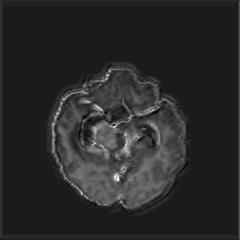

Deep Active Lesion Segmentation

[45]: Lesion segmentation is an important problem in computer-assisted diagnosis that remains challenging due to the prevalence of low contrast, irregular boundaries that are unamenable to shape priors. We introduce Deep Active Lesion Segmentation (DALS), a fully automated segmentation framework that leverages the powerful nonlinear feature extraction abilities of FCNs and the precise boundary delineation abilities of ACMs. Our DALS framework benefits from an improved level-set ACM formulation with a per-pixel-parameterized energy functional and a novel multiscale encoder-decoder CNN that learns an initialization probability map along with parameter maps for the ACM. We evaluate our lesion segmentation model on a new Multiorgan Lesion Segmentation (MLS) dataset that contains images of various organs, including brain, liver, and lung, across different imaging modalities—MR and CT. Our results demonstrate favorable performance compared to competing methods, especially for small training datasets. -